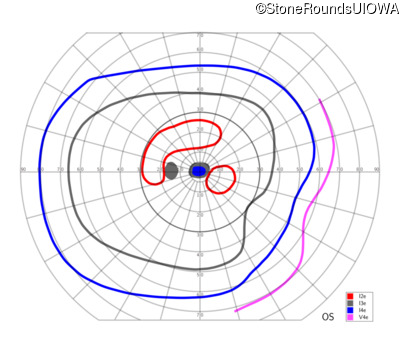

This 52 year old man had normal vision until his mid 30's when he began to have trouble distinguishing colors. the issuing 10 years he had a gradual loss of visual acuity accompanied by increasing photophobia.

| Age at visit: 64 years |